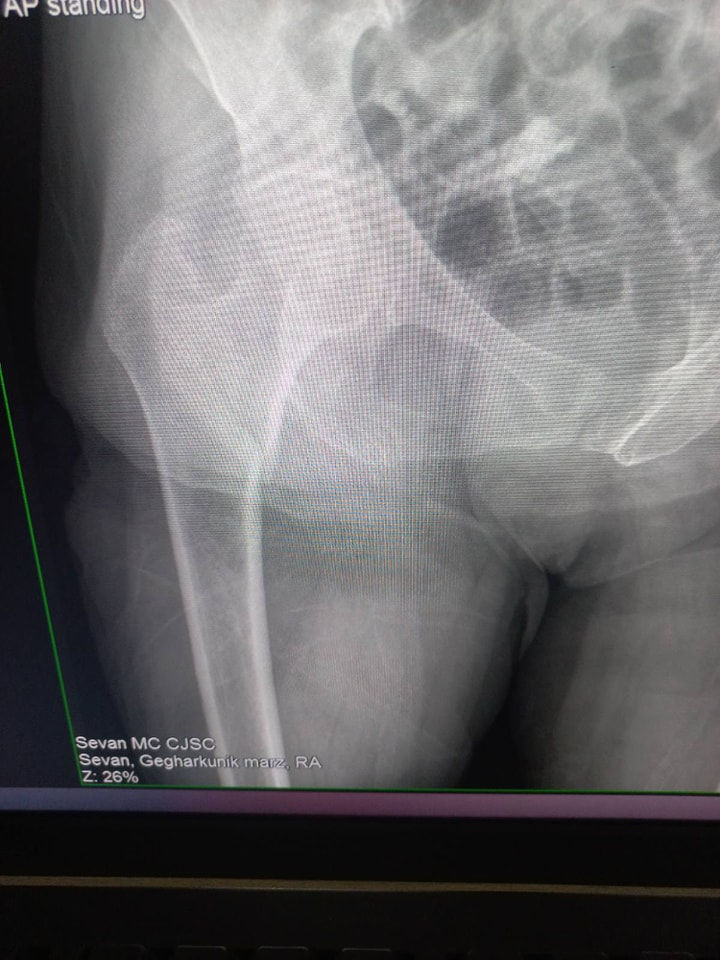

Ազդոսկրի կոտրվածք։

Կինը , ով Սևանի բժշկական կենտրոն է տեղափոխվել ազդոսկրի փակ կոտրվածքով, գանգատվում էր սուր ցավերից, տեղաշարժման սահմանափակումից։ Մեր մասնագետների գրագետ և համատեղ աշխատանքի շնորհիվ անմիջապես կատարվել է վիրահատական միջամտություն , կոտրված մասը ֆիքսվել է DHS հարթակով և պտուտակներով ։ Վիրահատական և հետվիրահատական ընթացքը անցել է հարթ, հիվանդը հաջորդ օրվանից քայլել է քայլակների օգնությամբ։

Վիրահատող բժիշկ` Ջանիկ Եղիազարյան